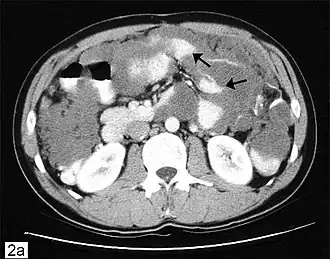

Компьютерная томограмма брюшной полости с изображением псевдомиксомы брюшной полости с рассеянными перитонеальными массами (стрелки).

Данное заболевание часто выявляется при хирургических операциях, проводимых по другим показаниям (удаление грыж), при этом опытный патолог может подтвердить диагноз. На последующих стадиях рассеянные опухоли пальпируются в абдоминальной области. Может выявляться вздутие живота, а также «желеподобный живот»[1] (сленговый медицинский термин, используемый для данного заболевания). В силу редкости заболевания, важна постановка точного диагноза для назначения соответствующего лечения. Диагностические процедуры могут включать проведение компьютерной томограммы, гистологического и иммуногистохимического исследования образцов, полученных при проведении диагностической лапароскопии. В качестве косвенных признаков может быть использовано проведение анализов крови на выявление онкомаркеров (РЭА, CA242). В большинстве случаев гастроскопия и колоноскопия оказываются неэффективными диагностическими средствами, поскольку рак аппендикса поражает брюшную полость, но не толстый кишечник (следует иметь в виду имеющиеся сообщения о редких случаях распространения рака аппендикса на кишечник). Ирригоскопия в ряде случаев указывает на дисфункцию илеоцекального клапана, расположенного в непосредственной близости от аппендикса. Позитронно-эмиссионная томография может быть использована для оценки злокачественной муцинозной аденокарциномы, однако данный тест не подходит для оценки доброкачественной разновидности опухоли, поскольку не может выявить теневое изображение новообразования. Магнитно-резонансная томография в настоящее время адаптируется для мониторинга заболевания, однако обычные магнитно-резонансные томографы как правило не используются в качестве диагностического инструментария. Диагноз также может быть подтвержден в патологических исследованиях.